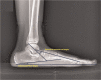

Idiopathic flatfoot is common in infants and children, and patients with this condition are frequently referred to pediatric orthopedic clinics. Flatfoot is a physiologic process, and that the arch of the foot elevates spontaneously in most children during the first decade of life. To achieve a consensus as the rate of spontaneous improvement of flatfoot, the present study aimed to estimate the rate of spontaneous improvement of flatfoot and to analyze correlating factors.We reviewed the records of patients examined between May 2013 and May 2019 so as to identify those factors associated with idiopathic flatfoot below 12 years of age. We included patients with who had been followed for >6 months, and those for whom ≥2 (anteroposterior and lateral) weight-bearing bilateral radiographs of the foot had been obtained. The progression rates of the anteroposterior (AP) talo-first metatarsal angle, talonavicular coverage angle, lateral talo-first metatarsal angle, and calcaneal pitch angle were adjusted by multiple factors using a linear mixed model, with sex, body mass index, and Achilles tendon contracture as the fixed effects and age and each subject as the random effects.We found that 4 of the radiographic measurements improved as patients grew older. The AP talo-first metatarsal angle, talonavicular coverage angle, and the lateral talo-first metatarsal angle decreased, while the calcaneal pitch angle increased. The AP talo-first metatarsal angle (P < .001), talonavicular coverage angle (P < .001), and lateral talo-first metatarsal angle (P < .001) improved significantly; however, the calcaneal pitch angle (P = .367) did not show any significant difference. In general, the flatfeet showed an improving trend; after analyzing the factors, no sex difference was observed (P = .117), while body mass index (P < .001) and Achilles tendon contracture (P < .001) showed a negative correlation.The study demonstrated that children's flatfeet spontaneously improved at the age of 12 years. It would be more beneficial if the clinician shows the predicted appearance of the foot at the completion of growth by calculating the radiographic indices and identifying the correlating factors in addition to explaining that flatfoot may gradually improve. This will prevent unnecessary medical expenses and the psychological adverse effects to the children caused by unnecessary treatment.